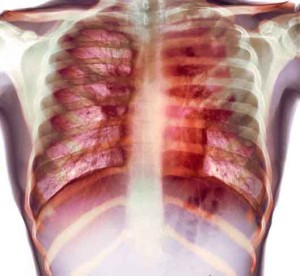

Tubercolosi: al via l’ultimo trial molecola che contrasta la forma più resistente.

Potrebbe iniziare entro fine anno il trial di fase 3 della terapia per il trattamento della tubercolosi multiresistente sviluppata dall’Ong Tb Alliance.

Lo ha affermato la stessa associazione, secondo cui parte dei fondi necessari sara’ assicurata dalla Bill & Melinda Gates Foundation. La terapia attuale, spiega il comunicato di Tb Alliance, dura due anni e e prevede l’uso di oltre 24mila tra pilloel e iniezioni.tubercolosi Il ‘triplo cocktail’ in sperimentazione invece, che consiste nell’uso di due farmaci nuovi e di uno gia’ usato contro la malattia, riduce il tempo a sei mesi, e richiede l’assunzione di poche pillole al giorno.

“I risultati delle prime fasi della sperimentazione fanno ben sperare – spiega lo stesso Gates – adesso abbiamo bisogno di un ulteriore sforzo economico”. In tutto il test, che verra’ condotto in Asia, Africa e Europa orientale, dovrebbe costare circa 58 milioni di dollari. .